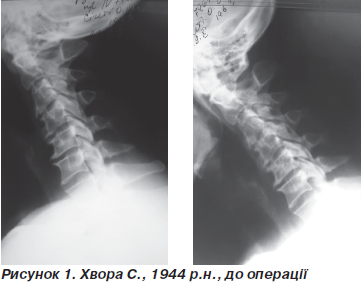

На рис. 1 наводимо приклад пацієнта.